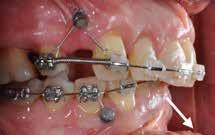

Objektivt anbefales behandling af det dybe bid, som ubehandlet forventes at forværres yderligere over tid. Patienten har ønske om behandling med æstetisk ortodontisk apparatur, alignere, og det vurderes muligt at behandle malokklusionen med alignere. Dog anbefales det generelt, at alignere undgås eller benyttes med væsentlige modifikationer af alignerens retention ved tandmobilitet, da dette ellers kan medføre jiggling, når aligneren tages af og på mange gange dagligt. På den anden side er der nogen evidens for, at alignerbehandling er associeret med bedre renhold og parodontal sundhed sammenlignet med fast apparatur (16).

Der planlægges alignerbehandling af begge kæber med intrusion af 1+1 og 2,1-1,2, nivellering af trangstilling UK med interproksimal reduktion (IPR) (Fig. 2 A, B) og senere IPR OK for reduktion af dark triangles mellem incisiverne efter nivellering. Patienten instrueres i at benytte alignere 20-22 timer/ dag med alignerskift hver 7. dag, og patienten ses hver 3.-8. uge under forløbet. Den første alignerserie består af 16 alignere for nivellering OK/UK og IPR i UK (Fig. 2). Efter denne serie planlægges IPR mellem incisiverne i OK for reduktion af dark triangles (Fig. 3) samt yderligere intrusion af OK og UK-fronten i 12 refinement-alignere. Patienten udviser god kooperation og er meget tilfreds med alignerapparaturet, som er mindre synligt end det faste apparatur (Fig. 4).

Behandlingen afsluttes med yderligere refinement-alignere for finindstilling af okklusionen, og efter 11 måneders ortodontisk behandling er der opnået normale relationer i alle tre